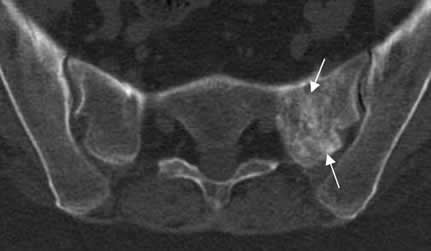

Fig 57 B. Fractura de stress.

RM coronal en STIR: Edema en el alerón del sacro izquierdo, por fractura de stress.

Fig 59. Fractura de stress.

TAC axial. Zona de fibrosis en el alerón izquierdo del sacro, resultado de reparación por fractura de stress.